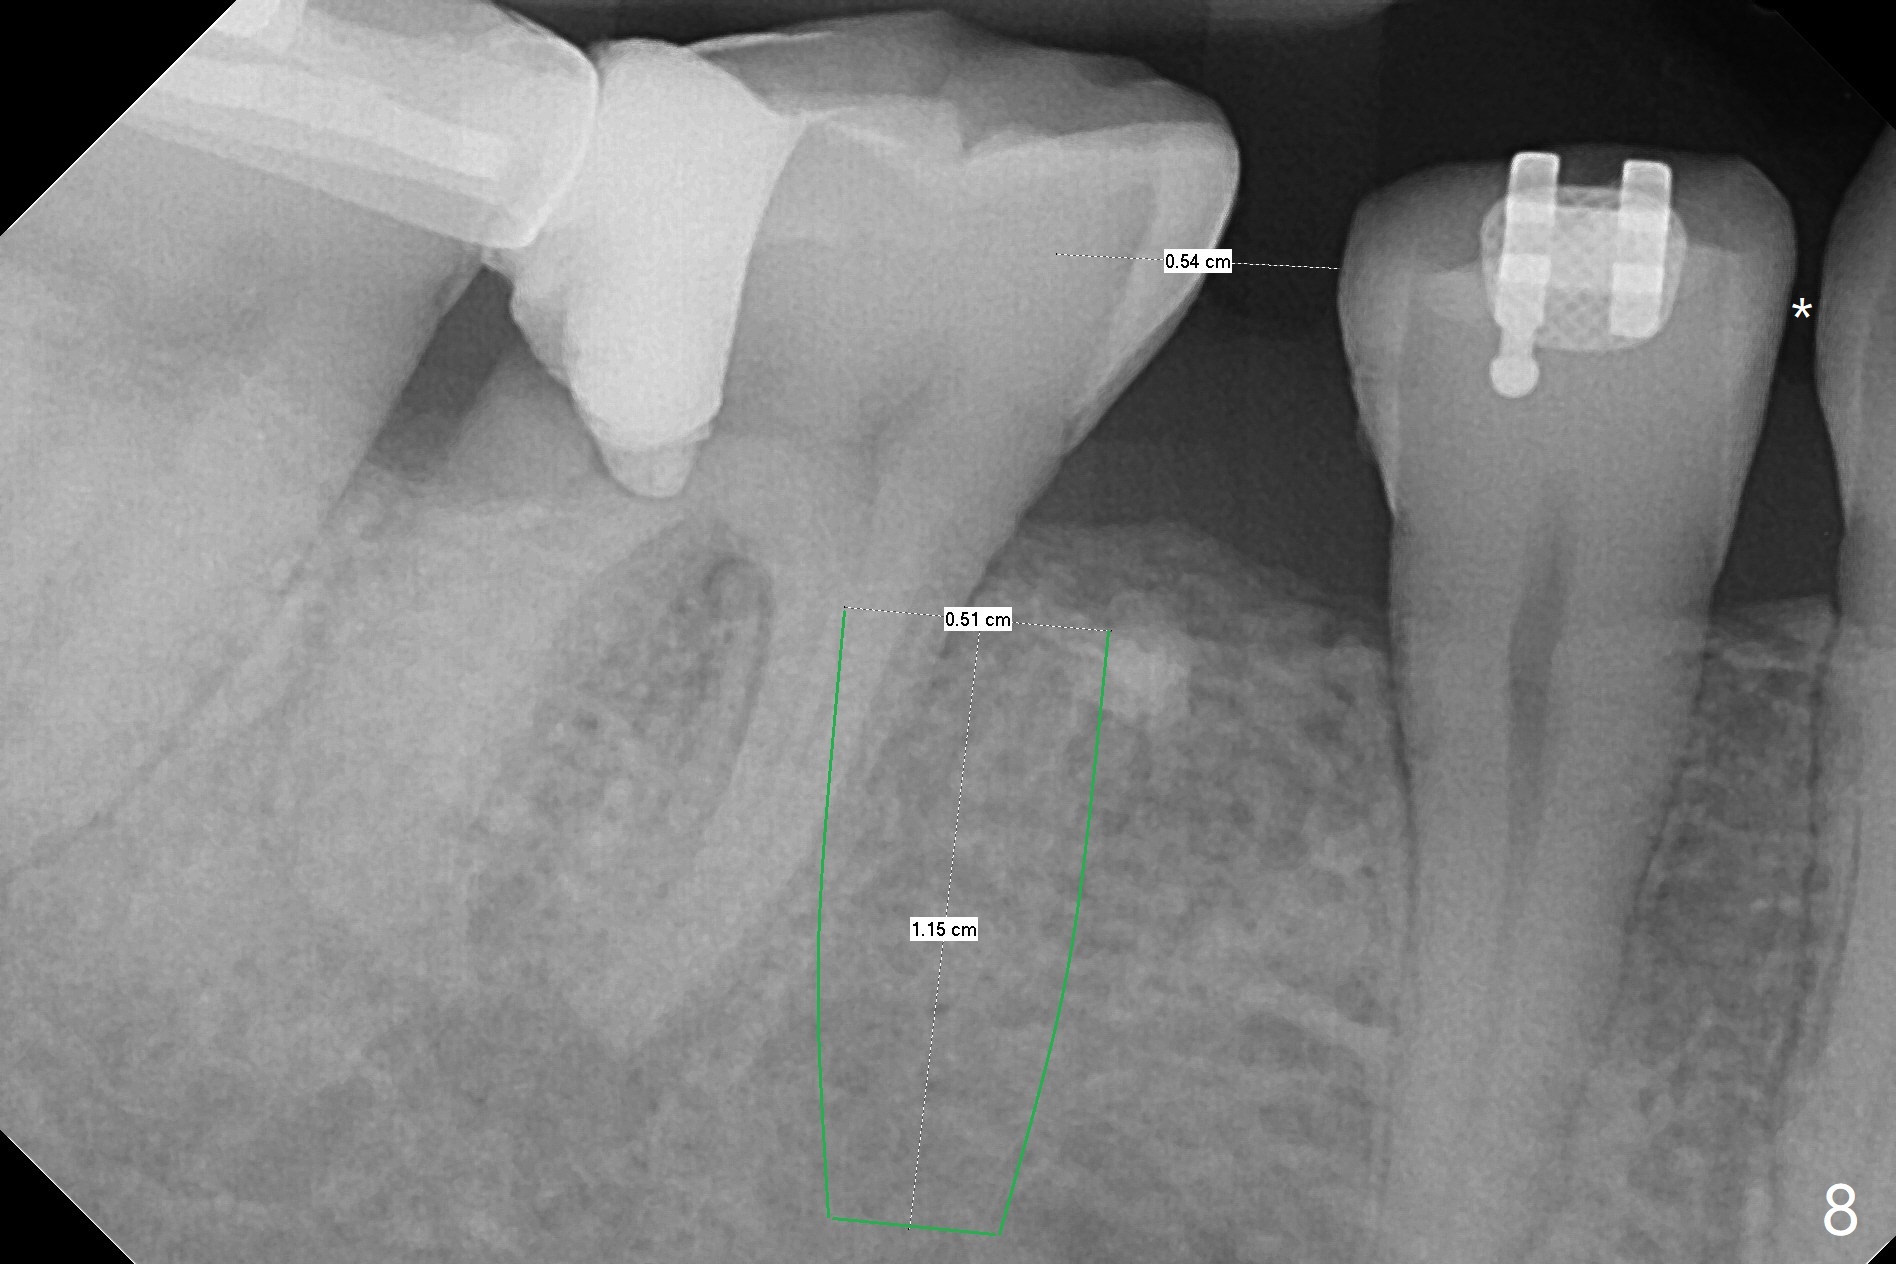

One year 4 months post banding (M) with 16x16 wires, UR3 is being distalized using UR7 as anchor (Fig.1), while the upper dental midline matches the facial one (Fig.2). The anterior overjet remains large (Fig.3). When UR3 is fully distalized, place posted wire to distalize U2-2 together. U2-2 distalization seems to be slow with one 16 mm closed coil spring each side (between 7 and post) 1 year 10 months post banding. Since the upper anterior PA shows mild root resorption at UR2 (Fig.4), a 14 mm closed coil spring is added each side (between 6 and post, Fig.5,6). LR6 has pain 2 years 2 months post banding (Fig.7). Debridement confirms non-salvageability; a 5x11.5 mm implant will be near the mesial root (Fig.8). Power chains for a month leads to closure of the gap between 3 and 4 (Fig.8-11). The space between 4 and 7 is 15 mm. A 12 mm 1st molar crown will be made, while the remaining 3 mm space will be closed by mesialization of 7 using 2 power posts mesial and distal to 6 and 7. Draw 2 tubes of blood. Make an incision to expose the mesial crest of 6.